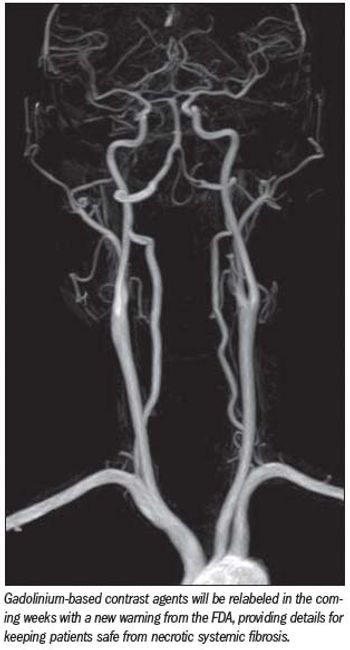

Five years after the first reports linking gadolinium-based MRI contrast agents to nephrogenic system fibrosis (NSF), separate presentations of post-marketing data from manufacturers and an independent prospective study supported by agencies in France have validated the low-risk status of the contrast agent Dotarem (Gd-DOTA).